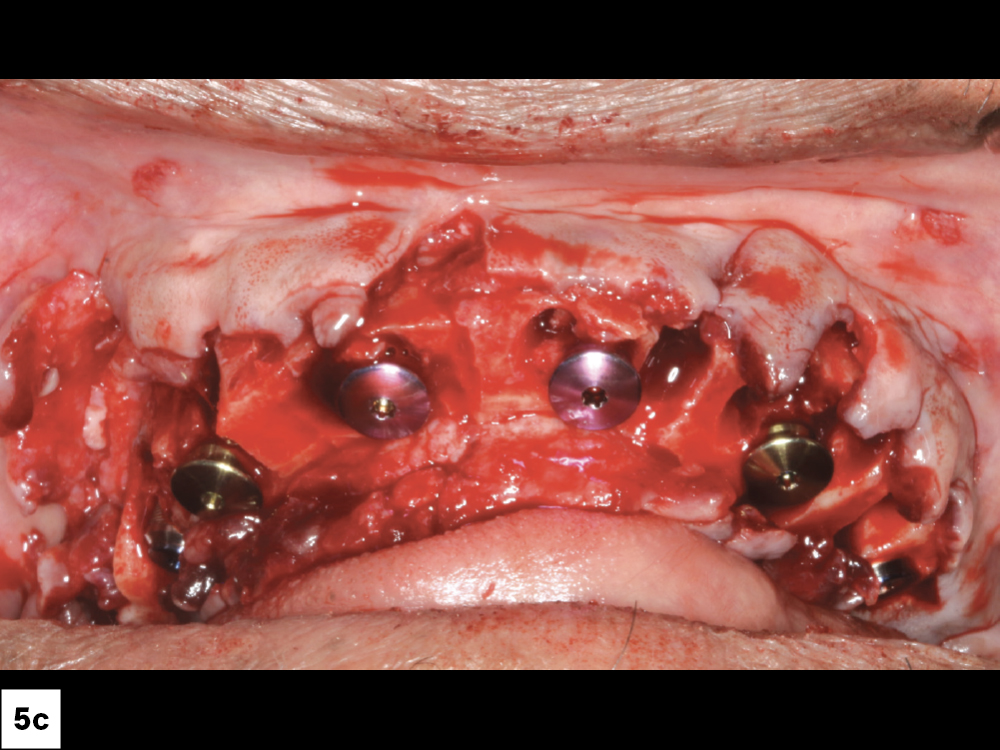

The osteotomy guide was then passively and completely seated, allowing for precise positioning of the implants.

Implant sites were created using the sequential drills in the Glidewell HT™ Implant Guided Surgery System (Glidewell Direct; Irvine, Calif.).

Each implant was placed at a torque of 25 Ncm. I then threaded 3-mm-tall healing abutments into place, according to the digital treatment plan provided by the team at Glidewell.

Figures 5a–5c: The osteotomy guide was then passively and completely seated, allowing for precise positioning of the implants. Implant sites were created using the sequential drills in the Glidewell HT Implant Guided Surgery System (Glidewell Direct; Irvine, Calif.). Each implant was placed at a torque of 25 Ncm. I then threaded 3-mm-tall healing abutments into place, according to the digital treatment plan provided by the team at Glidewell.